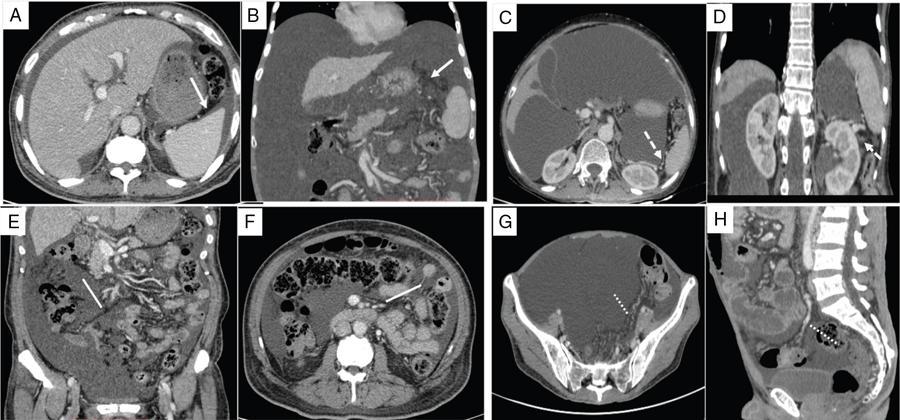

Shivsamb Jalkote, Slesha Bhalja, Disha Lokhandwala, Mansi Jantre, Karthik Ganesan Peritoneum is involved in a diverse group of primary as well as secondary pathologies ranging from the infective/inflammatory spectrum to malignancies. Peritoneal diseases are both common and potentially life threatening, and yet often get neglected in routine evaluation, due to the complex peritoneal anatomy and sometimes subtle imaging manifestations. The radiologist forms an integral part of the multidisciplinary team dealing with peritoneal pathologies and hence, having a lucid understanding of peritoneal anatomy, pathways of disease spread and different treatment options is paramount for an accurate radiological analysis. All three major serosal cavities (pleural, pericardial and peritoneal) of the body are derived from a single coelomic cavity, which is lined by a continuous mesothelium. At 2 weeks of gestational age, during the gastrulation stage, the embryo is a trilaminar disc, composed of the endoderm, mesoderm and ectoderm. During this stage, the development of the coelomic cavity commences as a consequence of morphological changes in the mesodermal cells leading to a coalition of the intercellular spaces. Peritoneum originates from mesoderm with its parietal layer developing from somatic mesoderm and visceral layer developing from splanchnic mesoderm. Initially, the peritoneum is an empty sac into which the growing gut tube protrudes (at 3 weeks of gestational age), resulting in the formation of the dorsal mesentery (formed by the fusion of two layers of the splanchnopleuric mesoderm) by which the gut tube is suspended lengthwise. The mesodermal cells opposed to the gut tube represent the future visceral peritoneum and those lining the body wall and the septum transversum form the future parietal peritoneum. Analogously, the ventral mesentery originates from the mesoderm of the septum transversum with the closure of the anterior abdominal wall, and, is short and not as extensive as the dorsal mesentery. The two mesenteries are aligned in the sagittal plane, subdividing the primitive peritoneum into right and left cavities, which are continuous anteriorly below the inferior edge of the ventral mesentery. With the development of various abdominal organs as buds from the gut tube, the capacity of the abdominal cavity diminishes, pushing the midgut loop into the umbilical cord. This physiologic herniation of the midgut takes place at the 6th week of gestation. Simultaneously, as the peritoneum drapes over the developing organs, there is compartmentalization of the cavity and a pattern of folds develops that eventually form the peritoneal ligaments. The majority of these ligaments arise from the ventral or dorsal mesentery. As the hepatic bud develops within the ventral mesentery, derivatives of the ventral mesentery can be divided based on their relation to the liver. The gastrohepatic ligament (lesser omentum) develops dorsally and the falciform, coronary, and triangular ligaments develop ventral to the liver. Conversely, the dorsal mesentery spans between the gut tube and the posterior abdominal wall, and the spleen and pancreatic tail develop within it. In congruence, it forms the gastrophrenic, gastrosplenic and splenorenal ligaments and peritoneal folds of the small and large intestines. As stated earlier, the dorsal mesentery has a relatively larger caudad extension and since the spleen develops in its upper portion, the rapidly growing mesentery beyond the spleen forms the greater omentum. Finally, the differential growth of the greater curvature of the stomach and the right hepatic lobe results in rotation of the abdominal organs and their mesentery, and the cephalad portion of the peritoneal cavity is divided into a larger ventral cavity, called the greater sac, which caudally communicates with the common peritoneal cavity, and a smaller dorsal cavity called the lesser sac. The key aspects of peritoneal development are summarized in Flowchart 8.6.1 and Fig. 8.6.1. Laparoscopy remains the gold standard in the assessment of peritoneal disease, however, it is an invasive technique, and has certain diagnostic limitations including the inability to assess parenchymal diseases, extraperitoneal diseases, and also has limited utility in the presence of adhesions. Hence laparoscopy is not recommended as the first-line modality and has been replaced by cross-sectional imaging in routine clinical practice. The role of imaging is primarily to assess disease burden in terms of volume and extent and to identify surgically nontreatable disease, which reduces open and shut laparotomies. Peritoneal metastatic disease burden is assessed using peritoneal carcinomatosis index (PCI) both surgically as well as using cross-sectional imaging, details of which will be discussed subsequently. CT, MRI and PET/CT are all commonly used imaging modalities, however, there is no singular universally accepted reference imaging standard for the peritoneal disease. In a recent meta-analysis evaluating the diagnostic performance of imaging in the detection of peritoneal metastasis (PM), authors concluded that MRI (DWI) and PET/CT show comparable diagnostic performance in gastrointestinal and ovarian cancer malignancies however the widespread availability of MRI makes it the more likely imaging modality of choice in the future. The results of this study are summarized in Table 8.6.1. Conventional imaging including radiography and barium studies have a poor diagnostic yield in evaluating peritoneal pathologies. Abdominal radiographs are usually restricted for identifying pneumoperitoneum and bowel obstruction in the setting of acute abdominal pain. Diffuse increase in radio-opacity of the abdomen, poor definition of soft tissue shadows (psoas, liver and spleen), bulging flanks along with medial displacement of small bowel loops from the properitoneal fat stripe are indirect markers of large ascites which can prompt further evaluation with ultrasonography. Indirect features of peritoneal disease on barium studies include mass effect and displacement of adjoining bowel loop, narrowing of bowel loop with bowel dilatation along with nodularity, spiculation, or tethering of adjacent mucosal folds or haustra with sacculation of the uninvolved contralateral border. Barium studies have fallen out of favour in routine radiological practice owing to the widespread use of cross-sectional imaging. Ultrasonography (US) is a readily available and relatively inexpensive imaging tool. Traditionally its role in the evaluation of peritoneal pathologies is limited as US beam gets strongly reflected at the interface of air and visceral structures which leads to obscuration of underlying structures. US remains the primary imaging modality in the evaluation of an acute abdomen and is useful in detecting of ascites, focal lesions and any focal abnormality at the site of tenderness. US has the unparalleled advantage of providing real-time assistance in performing imaging-guided procedures such as paracentesis and peritoneal biopsies. US can be used in characterization of focal lesions (as solid, solid-cystic and cystic) and assessment of internal vascularity using colour Doppler. Transvaginal US provides a good overview of pathologies involving pouch of Douglas besides the uterus and adnexa. Experienced and skilled sonologists can detect omental thickening, peritoneal nodules and small surface deposits using high-frequency transducer (Fig. 8.6.2). Endoscopic US allows assessment of diseases involving peritoneal ligaments besides assistance in a guided biopsy. The reported sensitivity, specificity and accuracy of EUS-FNA versus CT/MRI in detecting PM was 91% versus 28%, 100% versus 85% and 94% versus 47%, respectively. CT is the most commonly employed imaging modality in the evaluation of peritoneal pathologies due to its widespread availability, fast acquisition and high spatial resolution. Current generation multidetector CT scanners (64 slices and above) offer very thin collimation, leading to the acquisition of near isotropic volumetric data which allow reformations in coronal and sagittal images without any added imaging time. It is the modality of choice for preoperative staging in most primary abdominal and pelvic malignancies (e.g. stomach, appendix, ovary) owing to its ability to detect local and regional infiltration, nodal involvement and distant metastases. CT is also used to evaluate PCI and detect disease in critical and occult locations, thus significantly altering further management strategies. CT is the most common imaging modality used in postoperative surveillance and evaluation of postoperative recurrence. CT protocol includes administration of both enteric contrasts (oral and rectal) and intravenous contrast (Table 8.6.2). Optimal bowel distension is key as collapsed loops can mimic disease and also mask the serosal and endoluminal disease. Often, a CT scan of the chest is performed as an adjunct to rule out pleuroperitoneal/transdiaphragmatic dissemination. Helical (≥64 slice scanner) Dual energy scanner if available As thin as possible (≤1 mm) Same as section thickness without gap From xiphisternum to pubic symphysis Chest included if suspicion of thoracic involvement 1 L of positive oral contrast over duration of 60 minutes and 500 mL of positive rectal contrast on table before administration of IV contrast 1.5–2 mL/kg of nonionic contrast with high iodine concentration (≥ 300) at rate of 3–5 mL/sec Unenhanced imaging not recommended. Monophasic acquisition at 60 seconds usually sufficient in majority cases Arterial phase at 20 seconds acquired for arterial assessment Delayed phase in cases of ureteric obstruction, slow bowel transit and suspected leak. Axial 1 mm thickness, multiplanar reformats in coronal and sagittal planes at 1 mm MIP or 3D volumetric sections for vascular assessment There is a wide range of reported diagnostic accuracy (sensitivity ranging from 25% to 100%, specificity ranging from 78% to 100%) of CT in the assessment of PM depending on the expertise of the reader and scanner type. In general, key factors affecting CT sensitivity include the size of lesion, the region of affection and presence of ascites. 64 slice scanners with multiplanar reformations allow 100% sensitivity and positive predictive value in detecting lesions measuring >5 cm, which partly diminishes for lesions between 0.5 cm and 5 cm in size with sensitivity and positive predictive being 83% and 93%, respectively. It receives the most criticism in the evaluation of lesions < 0.5 cm with significantly low sensitivity and positive predictive value (43% and 76%, respectively). There is also a great degree of variation in sensitivity based on the anatomical location of the disease. In a study by Koh et al., the detection rates ranged from 8% to 67%, depending on the region involved; only the epigastrium exceeded 60%, with the small-bowel disease being the most poorly visualized (8%–14%). The sensitivity for tumour detection in epigastrium, greater omentum and under surfaces of the diaphragms was 60%–90%, while it was 50%–70% in the retroperitoneum and pelvis, and small bowel-mesentery involvement was detected in merely 20%–50% of cases. These are noteworthy findings, as small-bowel involvement has major implications on outcome and is one of the limiting factors for complete cytoreduction. Poor soft tissue resolution of CT doesn’t allow accurate differentiation between mucinous deposits from ascites. Administration of positive enteric contrast can mask calcified serosal deposits. DECT uses two separate x-ray energy spectra and allows characterization of tissues based on their differences in attenuation properties at different energies. Though the role of DECT in the assessment of abdominal pathologies is increasingly reported in the literature, there are very limited data available on its application in assessment of peritoneal pathologies. The combination of iodine overlay with conventional imaging has shown a better specificity in differentiating PM from benign peritoneal entities, and hence can be particularly useful in the postoperative setting. MR imaging offers excellent soft tissue resolution, multiplanar capabilities and avoids exposure to ionizing radiation, making it an attractive tool for evaluation of peritoneal diseases. MRI is better suited and can be problem solving in visualization of smaller lesions (<1 cm) and assessment of relatively concealed areas such as subphrenic, mesenteric and bowel serosa. Unenhanced T1- and T2-weighted images can show larger peritoneal deposits and masses but are relatively insensitive for the depiction of smaller lesions. The combination of diffusion-weighted imaging (DWI) and delayed gadolinium-enhanced MR imaging is considered the most accurate technique for detecting peritoneal tumours (Fig. 8.6.3). MRI protocol for assessment of peritoneum has been detailed in Table 8.6.3. In a study by Low RN et al., MRI PCI correctly categorized tumour volume in 91% of patients compared to surgical PCI, as opposed to 50% with CT. In addition, MRI demonstrated per site sensitivity of 95%, specificity of 70% and accuracy of 88%, while CT showed a corresponding per site sensitivity of 55%, specificity of 86% and accuracy of 63%. MRI PCI has also shown to have better prediction of intraoperative burden of disease for invasive appendiceal and peritoneal mesothelioma histologies as compared to CT-PCI. *This general imaging protocol is based on 3 T MRI Siemens system, covers both abdomen and pelvis. Protocol is modified depending on primary disease and type of scanner. Low RN. Preoperative and surveillance MR imaging of patients undergoing cytoreductive surgery and heated intraperitoneal chemotherapy. Journal of gastrointestinal oncology. 2016 Feb;7(1):58. The higher cellularity of majority of peritoneal nodules results in restriction of water movement and corresponding high signal intensity on DW images. On the higher b-value images, bowel contents are suppressed and the serosal and peritoneal tumours become hyperintense. DWI is also useful to demonstrate associated lymphadenopathy, hepatic and osseous metastases. In a study by Zhang et al., in PC of colorectal carcinoma, DWI demonstrated sensitivity of 69.4%, 91.3% and 100% for lesions measuring <0.5 cm, 0.5–5.0 cm and >5 cm, respectively. The overall sensitivity, specificity and accuracy of DWI for the detection of peritoneal tumours were 80.3%, 84.5% and 82.1%, respectively. DWI/MRI is also superior in demonstrating lesions involving small bowel wall, with an accuracy of 92%–95% versus 48% for CT. Reported negative predictive value of DWI for small bowel serosal metastases is 100%. Whole-body DWI/MRI was highly accurate for the prediction of inoperability (PPV 100%, NPV 90.3%) and was capable of detecting metastases both inside and outside the abdominal cavity. Peritoneal tumours enhance slowly and are best depicted on the final set of images obtained about 5 minutes following gadolinium administration. The increased conspicuity of these enhancing peritoneal tumours improved detection of small tumours that are often missed on CT scans. For this reason, perfect breathhold is essential while obtaining the final set of images and if images are acquired later, contrast that has diffused into the ascitic fluid can obscure smaller lesions. The high-contrast conspicuity of fat-suppressed and delayed gadolinium-enhanced MRI makes it the imaging modality of choice in depicting subcentimetre deposits (including those measuring <5 mm), and also deposits in anatomically concealed sites (e.g., subphrenic, mesenteric and bowel serosa). Gadolinium-enhanced MRI has higher sensitivity in detecting peritoneal lesions <1 cm which is about 85%–90% compared to 22%–33% for CT. Despite the clear superiority of MRI over CT, the major detractors against MRI are the long exam times and the higher expense burden. Longer acquisition times can lead to motion artefacts related to respiration and bowel peristalsis compromising detection of smaller lesions. MRI is contraindicated in patients with pacemakers, cochlear implants and claustrophobic patients with some exceptions. DW-MRI is less sensitive in special histological subtypes such as signet ring cell and mucinous adenocarcinoma due to their limited restricted diffusion. The combined use of FDG-PET with anatomical CT imaging, provides the added benefit of qualitative and semiquantitative metabolic analysis (Fig. 8.6.4). PET/CT has an established role in staging of most of the primary tumours of the chest, abdomen and pelvis. It is also helpful in assessing malignant ascites or PM of an unknown primary. In disseminated malignancies, it can localize the optimal site for biopsy depending upon metabolic activity of the lesion. PET/CT should be used selectively in preoperative assessment of patients with large tumour volumes and poor prognostic histologies being considered for CRS and HIPEC to rule out extra abdominal metastases. It can also detect extraabdominal metastases, including mediastinal and supraclavicular nodes, and other organ sites, such as bone and brain. It can also detect nodal involvement in normal-sized lymph nodes seen on conventional cross-sectional imaging. PET/CT also plays a role in disease surveillance and assessment of response to neoadjuvant chemotherapy. This is particularly relevant in malignancies where anatomical changes are so small that measurement of size change alone becomes unreliable and also in differentiating between residual/recurrent disease and postoperative changes after CRS and HIPEC. Besides oncological indications, PET/CT is also helpful in assessment of benign and inflammatory diseases to evaluate disease extent and also localize the site for biopsy. In cases of pyrexia of unknown origin, PET/CT has often been employed to demonstrate unsuspected peritoneal disease. Utility of PET/CT in peritoneal disease assessment is limited in developing counties due to its higher cost burden and lower accessibility. Certain histological subtypes such as mucinous and signet ring cell carcinomas show low FDG uptake making PET/CT less sensitive. Low metabolic uptake in these subtypes is thought to be due to low tumour cell density, higher content of metabolically inert mucin and lack of expression of glucose transporter Glut-1. This is more relevant in context of colorectal malignancy where mucinous carcinoma and signet ring cell carcinoma more frequently metastasize to the peritoneum compared to adenocarcinoma (48%, 51% and 20%, respectively). PET/CT is prone to artefacts caused by misregistration between the CT and PET images which can lead to inaccurate assessment of certain regions such as dome of diaphragm and structures adjoining the urinary bladder, making the detection of pelvic implants difficult due to partial volume effects. Implants against the small bowel and mesentery may be obscured by the physiological metabolic activity of bowel. Pretreatment PET/CT demonstrates a higher accuracy than CT for nodal and metastasis staging but has limited sensitivity to detect PM, especially when there is small-volume disease as only 13.6% of the nodules less than 0.5 cm were correctly identified by PET/CT. Table 8.6.4 summarizes role of different imaging modalities for assessment of peritoneal diseases. Peritoneum is the largest serosal membrane in human body with surface area of about 2.2 m2. It is composed of parietal and visceral layers which are continuous with each other, with parietal peritoneum lining the coelomic cavity and visceral peritoneum lining the visceral organ (Fig. 8.6.5). The peritoneum essentially minimizes friction, resists infection and stores fat, allows free movement of the abdominal viscera which gets restricted in presence of adhesions. Peritoneum acts as first line of defence in controlling disease spread, and, it exudes fluid and cells in response to injury or infection (peritonitis), to wall off or localize infection. In natural states, intraperitoneal spread of infection is limited by lymphoid aggregates and stomata on both the peritoneal layers. Omentum is commonly known as policeman of abdomen as it migrates to the site of infection and isolates affected area from healthy tissues. Iatrogenic violation of peritoneum following surgery can lead to recurrence along the operative incision scar sites and along the vaginal cuff following hysterectomy in pelvic malignancies. The parietal peritoneum is supplied by nerves (e.g. phrenic and thoracoabdominal) to the adjacent body wall, and is predominantly very sensitive to pain, which explains the typical referred shoulder pain from upper abdominal pathologies such as gall stones and pancreatitis. The visceral peritoneum is insensitive to pain and responds mainly to stretching. These two layers encompass a potential space, called the peritoneal cavity which contains approximately 50–75 mL of clear serous fluid. Peritoneal cavity is a closed space in males while in females it communicates with extraperitoneal pelvis through ostia of fallopian tubes allowing transport of ovum. This communication serves as natural route for ascending spread of sexual transmitted disease from genital organs into peritoneal cavity leading to pelvic inflammatory disease and uncommonly perihepatitis (Fitz–Hugh–Curtis syndrome). The invaginations of the peritoneum result into formation of three different types of structures namely ligaments, omentum and mesentery (Figs. 8.6.6–8.6.9) which serve as bridges that permit blood, lymph vessels and nerves to reach the viscera. Ligaments are double folds of peritoneum that connect one organ to another organ or to the abdominal wall and are named usually after the respective viscera. The liver, for example, is connected to the diaphragm by the falciform ligament, coronary ligament and right and left triangular ligaments. Mesenteries are double folds of peritoneum that suspend intestine to the posterior abdominal wall (retroperitoneum) such as the small bowel mesentery, transverse and sigmoid mesocolon. Omentum are double folds of peritoneum that extends from the stomach to other organs and include the greater and lesser omentum. Table 8.6.5 summarizes the peritoneal ligaments in abdomen and pelvis. In medical school days, the anatomy textbooks traditionally divided abdomen and pelvis into tricompartmental model comprising of peritoneal cavity, retroperitoneum and extraperitoneal spaces. This model is good for basic understanding of anatomy and confinement of certain disease processes but fails to explain spread of diseases from retroperitoneum to peritoneum besides spread of some disease processes within peritoneal cavity itself. Considering these shortcomings of conventional description of anatomy, the unifying concept of subperitoneal space has evolved in literature and is getting accepted increasingly. As per this concept, abdomen and pelvis are divided in two spaces peritoneal cavity and subperitoneal space which are separated from each other by peritoneum. Subperitoneal space (Fig. 8.6.10) is large anatomically continuous potential space which connects peritoneal cavity with retroperitoneum. It constitutes the subserosal areolar tissue and fat tissue lining the inner surfaces of the peritoneum and the abdominopelvic musculature. The omentum, ligament and mesentery are the interconnecting peritoneal folds building the subperitoneal space. All the abdominal and pelvic organs along with their vascular, lymphatic and nervous supplies are situated within subperitoneal space. With this concept, we want to correct the common misconception of intraperitoneal organs as in strict terminology there is no organ within the peritoneal cavity itself. It is imperial to understand differences between peritoneal and subperitoneal spaces as these are mutually exclusive spaces having distinct patterns of disease spread which we will discuss in subsequent sections. In resting state, peritoneal cavity is collapsed and thus not visible on routine imaging. Peritoneal cavity usually gets distended due to disease processes composed of fluid, air or masses. The peritoneal cavity is divided into two parts: the greater sac and the lesser sac which communicate with each other via an epiploic foramen (of Winslow). The greater sac forms main peritoneal cavity and extends from the diaphragm down into the pelvis. The lesser sac is small diverticulum and lies between stomach and pancreas. For better understanding, abdominal peritoneal cavity is divided into supra- and inframesocolic compartments, communicating with pelvic peritoneal cavity which is further divided by other peritoneal folds and reflection (Flowchart 8.6.2, Figs. 8.6.10 and 8.6.11). Supramesocolic compartment (Fig. 8.6.12) is situated between the diaphragm and transverse mesocolon. It is arbitrarily divided into right and left supramesocolic peritoneal spaces, which can be further subdivided into a number of subspaces by upper abdominal organs and peritoneal ligaments. Right supramesocolic space is divided into three subspaces: right subphrenic space, right subhepatic space and lesser sac. Right subphrenic space is partially separated from right subhepatic space by right triangular ligament. Right subphrenic space is situated between right hemidiaphragm and right lobe of liver (superior, anterior and right lateral surfaces). It is limited posteriorly by the coronary ligament and medially by the falciform ligament with the latter separating it from the left subphrenic space. Right subhepatic space is situated inferior to right lobe of liver and has anterior and posterior components. Anterior component is limited inferiorly by transverse mesocolon whereas the posterior component extends anterior to right anterior perirenal fascia. Posterior component of right subhepatic space is commonly known as hepatorenal pouch (of Morrison) and forms most dependent site in supine position, thus being a common site of fluid accumulation. The right subhepatic space freely communicates with right subphrenic space superiorly and right paracolic gutter inferiorly. Lesser sac (also known as omental bursa) is situated superior to the transverse mesocolon, anterior to pancreas and posterior to the lesser omentum, stomach and gastrocolic ligament. Lesser sac (Fig. 8.6.13) communicates with right subhepatic space (of greater sac) via epiploic foramen which is bounded by IVC posteriorly, free margin of hepatoduodenal ligament anteriorly, D1 (first part of duodenum) caudally and caudate lobe of liver rostrally. Division of lesser sac into smaller superior compartment (superior recess) and larger inferior compartment (inferior recess and splenic recess) is accomplished by prominent crescentic gastropancreatic fold (peritoneal fold overlying common hepatic and left gastric artery) which extends from neck of the pancreas to the upper part of lesser curvature of stomach. The superior recess is situated to the right of midline above pancreas and posterior to lesser omentum. It surrounds the medial aspect of the caudate lobe and superiorly into the fissure for the ligamentum venosum. Splenic recess extends to splenic hilum, and is limited by gastrohepatic ligament (anterior), gastrosplenic ligament (lateral) and splenopancreatic ligament (posterior). Inferior recess is located to left of midline, separates stomach from the pancreas and transverse mesocolon. In few cases, an infrapancreatic part can be seen due to persistence of inferior recess within the greater omentum or due to downward bowing of transverse mesocolon. Left supramesocolic space is wider than right supramesocolic space and is limited above by left hemidiaphragm and below by transverse mesocolon and phrenicocolic ligament. Left supramesocolic space (subphrenic part) is medially separated from right supramesocolic space by falciform ligament and inferiorly from left paracolic gutter by phrenicocolic ligament. It is divided into four communicating subspaces: anterior left subphrenic space, posterior left subphrenic space, anterior left perihepatic space and posterior left perihepatic space. All these spaces communicate with each other. The definitions of the boundaries of these spaces vary in literature. Anterior left subphrenic space is situated between gastric fundus and left hemidiaphragm. Posterior left subphrenic space (also known as perisplenic space) surrounds spleen. Anterior left perihepatic space is situated between anterosuperior aspect of left lobe of liver and left hemidiaphragm. Posterior left perihepatic space (also known as gastrohepatic recess) is situated between inferior aspect of left lobe of liver and lesser omentum. Inframesocolic compartment (Fig. 8.6.14) extends below transverse mesocolon to the level of pelvic brim and is divided into large central part and smaller paracolic part (lateral recesses). Central portion of inframesocolic compartment is unequally divided by obliquely oriented small bowel mesentery leading to formation of smaller right inframesocolic compartment and larger left inframesocolic compartment. Right inframesocolic space terminates at the ileocaecal junction and does not communicate with pelvis. Left inframesocolic space is in communication with pelvic peritoneal spaces except at the sigmoid mesocolon attachment which offers partial barrier. Peritoneal recesses on the posterior abdominal wall lateral to the ascending and descending colon form right and left paracolic gutters respectively. Both paracolic gutters communicate freely with pelvic peritoneal spaces. Right paracolic gutter is deeper than left gutter and is in free communication with right supramesocolic space. Left paracolic gutter is partially limited from left supramesocolic space due to presence phrenicocolic ligament. Pelvis constitutes about one-third of the total volume of the peritoneal cavity and is most dependent part in both supine and erect positions. Inferiorly peritoneum drapes over fundus of urinary bladder, anterior and posterior surface of uterus and upper posterior vagina in females and anterolateral surface of the upper rectum leading to formation of different peritoneal spaces. The urinary bladder subdivides pelvis into anterior and posterior paravesical spaces. The anterior paravesical space is further compartmentalized by remnant of the urachus (median umbilical ligament), the obliterated umbilical arteries (medial umbilical ligament), and the lateral umbilical ligaments (inferior epigastric vessels) into five fossae: the right and left lateral and medial inguinal fossae and the supravesical fossa. The supravesical space is seen in midline with medial and lateral inguinal fossae placed on either side. The supravesical space lies above urinary bladder between the two medial umbilical folds, is usually occupied by small bowel loops and fundus of distended urinary bladder. Just lateral to the supravesical space is the medial inguinal fossa, located between the medial and lateral umbilical folds. The femoral ring is located inferolaterally and hence ascitic fluid in the medial inguinal fossa can extend into the femoral canal. Finally, the lateral inguinal fossa is located between the lateral umbilical fold and parietal peritoneum (which reflects over the vas deferens or round ligament). It usually contains the cecum or ileum on the right and sigmoid colon on the left. Extension of ascitic fluid into the inguinal canal can occur through the deep inguinal ring, located anteromedial to the lateral inguinal fossa. The posterior paravesical space is a larger recess situated between the urinary bladder and rectum. In women, uterus further divides it into smaller vesicouterine and larger rectouterine spaces. The vesicouterine space is located between the urinary bladder and uterus and is formed as the peritoneum drapes the uterine body and fundus and then runs over the urinary bladder (along its posterosuperior surface). It is continuous with the supravesical space anteriorly and its depth varies with the degree of urinary bladder distension. The rectouterine pouch (of Douglas) is delimited anteriorly by the uterus and broad ligaments and posteriorly by the rectum. Lateral to this cul-de-sac on either side are the uterosacral ligaments that run from the sacrum to the uterine cervix that separate the rectouterine pouch from the laterally located ovarian fossae. In men, the rectovesical pouch is formed as the peritoneum runs from the rectum to the posterior surface of the bladder. Posteriorly, the peritoneal reflection from the upper rectum runs to the pelvic sidewalls, forming right and left pararectal fossae, which vary in size with the degree of rectal distension. Analogous to the uterosacral ligaments in women, the rectovesical space is restricted by sacrogenital folds on either side, which extend from the urinary bladder to the sacrum. The rectovesical space and rectouterine space (pouch of Douglas) form most dependent areas in both in supine and standing positions in males and females, respectively (both in supine and standing positions). The key aspects of pelvic peritoneal spaces are summarized in Flowchart 8.6.3, Figs. 8.6.15 and 8.6.16. Peritoneal recesses represent small pockets or fossae in the peritoneal cavity bounded by folds of peritoneum and possibly represent developmental aberrations. Knowledge of these recesses is important as they can serve as pathways for internal hernias. Multiple peritoneal folds may surround fourth part of duodenum (D4) and duodenojejunal junction forming duodenal recess. Six major duodenal recesses include superior, inferior, paraduodenal, retroduodenal, duodenojejunal and mesentericoparietal recess. The superior duodenal recess is situated to the upper left side of fourth part of duodenum (D4) behind the superior duodenal fold at L2 level. Inferior mesenteric vein is situated behind lateral end of superior duodenal fold. Inferior duodenal recess is situated on left of D4 below DJ flexure and behind the inferior duodenal fold at L3 level. Inferior duodenal recess often exists in association with superior duodenal recess. Reported incidence of superior and inferior duodenal recesses is about 40%–50% and 70%–75%, respectively. Paraduodenal recess is seen on left side and slightly behind D4 bounded anteriorly by paraduodenal (falciform fold). Right free margin of paraduodenal fold contains the inferior mesenteric vein and an ascending branch of the left colic artery. This recess is seen in about 2%–3.8% cases and is site for left paraduodenal hernia. Retroduodenal recess as the name suggests situated behind the third and fourth parts of the duodenum and in front of abdominal aorta. Its orifice is bounded anteriorly by duodenoparietal fold. Retroduodenal space is largest among all the duodenal recesses and is seen in about 2.5% cases. Duodenojejunal recess is situated between the duodenojejunal flexure and root of transverse mesocolon, hence also known as mesocolic recess. Its boundaries include pancreas (superior), left renal vein (inferior) and left kidney (left). Its opening lies between two peritoneal folds, is directed inferiorly and to the right. Duodenojejunal recess is seen in about 20% cases and is almost never associated with other duodenal recesses. Mesentericoparietal recess is situated below third part of duodenum and behind the upper part of the mesentery. Its opening is bounded anteriorly by the fold of mesentery raised by the superior mesenteric artery. This recess is most rare among all with incidence of about 1%. It is the site for right paraduodenal hernia. The key aspects of duodenal recesses are summarized in Table 8.6.6 and Fig. 8.6.17. Peritoneal folds adjoining cecum result in formation of four main recesses: superior ileocaecal recess, inferior ileocaecal recess, retrocaecal recess and paracolic recess (Fig. 8.6.18). Surgically these recesses are important as they can be sites for internal herniation (except for paracolic sulci) or site of abscess formation in complicated appendicitis. Superior ileocaecal recess is bounded in front by the vascular fold of the cecum (containing anterior caecal vessels), behind by the ileal mesentery, below by the terminal ileum and on the right by the ileocaecal junction with its opening on left. Inferior ileocaecal recess is bounded in front by the ileocaecal fold (bloodless fold of Treves), above by the terminal ileum and its mesentery, to the right by the caecum, and behind by the upper part of the mesoappendix with its opening on left. Retrocaecal recess is bounded in front by posterior wall of cecum (and sometimes the proximal ascending colon), behind by the parietal peritoneum (posterior abdominal wall), and on either side by two caecal folds (parietocolic folds). Retrocaecal recess is largest among all the caecal recesses with its opening inferiorly and often contains appendix. Paracolic sulci represent variable one or more shallow lateral depressions in the peritoneum investing the cecum usually within the right paracolic gutter. This recess lies behind and inferior to the apex of inverted V-shaped root of sigmoid mesocolon with orifice opening inferiorly. Posteriorly, it is limited by parietal peritoneum of covering the left ureter at its iliac vessel crossing. This recess can be variable in size ranging from dimple to a small fossa in majority of the cases usually admitting little finger. It forms most common site of sigmoid mesocolon hernia. It can also be involved by peritoneal fluid and metastatic disease. Peritoneal and subperitoneal spaces are mutually exclusive spaces having distinct patterns of disease spread. Different pathways of the intraabdominal and extraabdominal disease spread are summarized in Table 8.6.7.